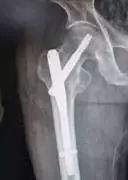

治愈百岁老人的髋部骨折——困难与挑战

无痛与微创

高龄老人髋部骨折传统的治疗方法是患肢制动或牵引,目前仅适用于内科疾病重、不能耐受麻醉和手术的患者及意识不清和不能自主活动的患者;存在治疗时间长、全身并发症多和病死率高等缺点。目前,为了让老人尽早恢复活动和自理能力,及时有效率的手术治疗已成为治疗老年髋部骨折的主要方法。

要减少老人手术带来的痛苦与风险,我们坚持采用先进的无痛和微创技术。手术损伤小,术后恢复快!